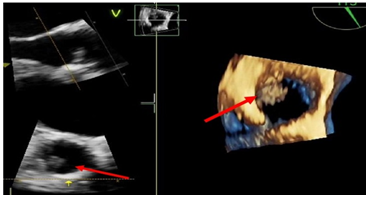

A 78-year-old woman with a history of a biological aortic prosthesis, implanted in 2016, and atrial fibrillation was admitted to the emergency department due to progressive worsening of low back pain for 3 weeks with irradiation to the lower limbs and severe gait limitation. The pain was poorly responsive to analgesics. She had no history of trauma. At the physical examination, she presented apyretic, tachycardic, sleepy, with degree III/VI systolic murmur without irradiation and palpation pain in thorny apophyses in D12 to L4. No sensory or motor deficit. Blood analyses revealed Hb: 9.9mg/dL, leukocytosis 10,800 with neutrophilia 83%, Protein-C-reactive 11mg/dL, VSG: 131mm/h, Cr: 2.4mg/dL, Urea 99.7mg/dL; LDH 313, CK: 506. Lumbar CT scan revealed "multiple and small millimetric osteolytic lesions in almost all of the lumbar somatic bodies and the left lateral slope of the upper S1 platform, some with rupture of the cortical bone." After hospital admission, there was a worsening of the general state of the patient with sudden onset of fever, tachycardia, and exacerbation of severe intensity low back pain associated with paraparesis and Janeway cutaneous lesions in the plantar region of the foot (Figure 1). There were no signs of acute heart failure. She performed an ECG with atrial fibrillation and a CT-EC without acute ischemic changes. Due to the high suspicion of endocarditis, blood cultures were collected, and a transesophageal echocardiogram was performed, revealing vegetation on the ventricular side of the biological prosthesis in aortic position without obstruction and without associated regurgitation or local complications (Figure 2). Given the new findings, it empirical antibiotic therapy with vancomycin and gentamicin was initiated and a lumbar spine magnetic resonance imaging was performed that showed “D12-L1 reduction in inter somatic height, vertebral platform irregularities, disc edema and diffuse alteration of the bone matrix signal of the D12 and L1 vertebral bodies (T2/STIR and hypoT1) with marked enhancement, translating inflammatory/infectious changes in the context of spondylodiscitis” (Figure 3) Hemocultures were positive for S. epidermidis methicillin-resistant.